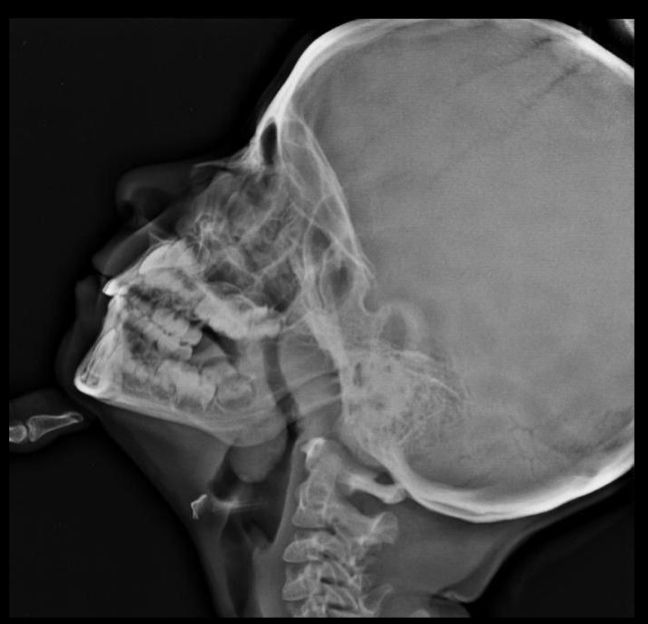

clx

facie adenoide:

Boca abierta

Cara alargada

Mordida abierta

Hundimiento de pomulos

Respiracion oral

Ronquido